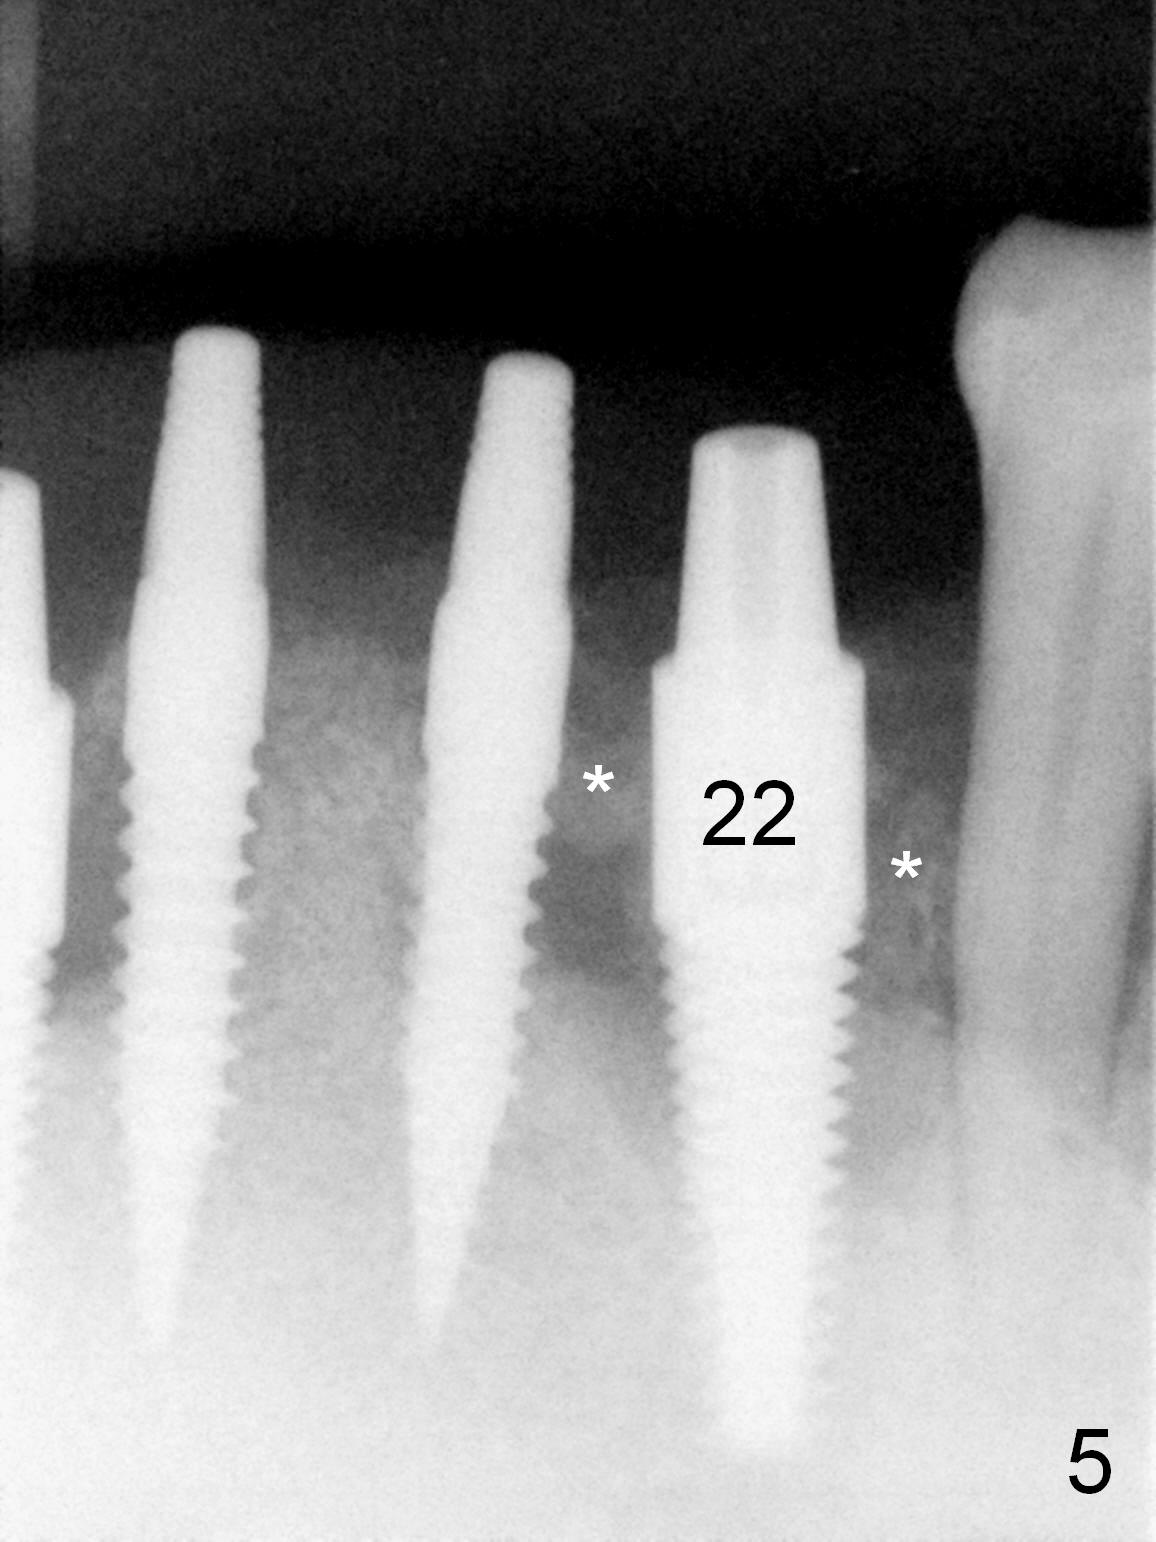

As expected, the bone density in the mandibular anterior region is found to be high during initial osteotomy (Fig.1-3).  Five implants are placed at the sites between #22 and 28 (Fig.4,5): 3x14(2) mm 1-piece (bone-level) implants in the incisor region; 4.5x17 mm 2-piece (tissue-level) ones in the canine/premolar area.  All of the implants are placed as lingual as possible.  Bone graft is placed (*).  Red dashed line: the superior border of the Inferior Alveolar Canal.  Immediate splinted provisional bridge is fabricated.  One week postop, periodontal dressing remains attached to the provisional and the gingiva.